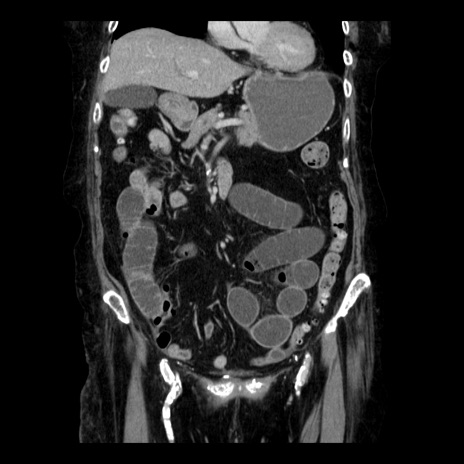

症例14(冠状断像)

【症例】 90歳代女性

【主訴】 腹痛・嘔吐

【現病歴】今朝から左側腹部痛を認めた。 経過観察していたが、嘔吐を認めたため来院。

【既往歴】 子宮癌術後

【身体所見】 意識清明、BP 127/54mmHg、P 98bpm Sp02 95%(RA)、BT 35.8°C、腹部平坦・軟腸ぜん動音聴取良好、右下腹部圧痛(+) 反跳痛なし

【データ】WBC 9800、CRP 0.46